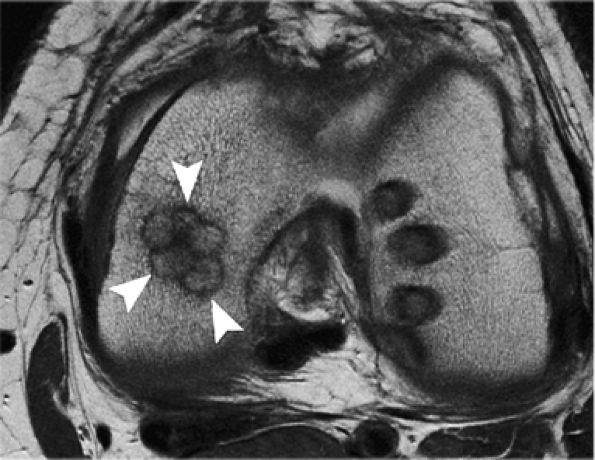

FIGURE 7.6 ● (A) Sagittal fat-suppressed T1-weighted gradient-echo MR image sequence of the knee demonstrates a focal high-grade partial-thickness cartilage defect overlying the medial femoral condyle (arrowheads). In the equivalent time required to acquire this single pulse sequence, cartilage-sensitive fast spin-echo MR sequences in two planes—sagittal (B) and coronal (C)—can be obtained, in which the depth of the lesion is much better delineated. (Reprinted by permission of SAGE Publications, Inc., from Am J Sports Med, in press.)

|